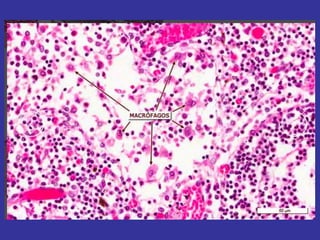

MACROFAGOS

• histiocito. Origen de monocitos ,

provenientes de la medula ósea ( Sistema

fagocitico mononuclear )

• Función Acción fagocítica eliminan

desechos celulares , agentes extraños.

partículas de carbón, bacterias, esporas

de hongos, pequeños parásitos Son

importantes agentes de defensa

•

Macrófagos

 capacidad fagocitica

 movilidad

Constituye un protector celular de importancia

en las respuestas inflamatorias locales.

En estudios realizados más recientemente,

se ha sugerido también que el macrófago

participa en la defensa del organismo

mediante la secreción de interferón y en la

reacción inmunitaria a través de la

colaboración intercelular.

Macrófagos . Diferentes tipos

Macrófagos o histiocitos del tejido conjuntivo laxo y

denso.

Células de Küpffer en los sinusoides hepáticos.

Macrófagos alveolares del pulmón o “células de polvo”.

Células dendríticas de los tejidos linfáticos.

Macrófagos del parénquima esplénico (bazo).

Células de Langerhans relacionadas con los epitelios

planos estratificados Epidermis

Células mesangiales del corpúsculo renal.

La microglia en el tejido nervioso.

Osteoclastos (macrófagos fusionados) del tejido óseo